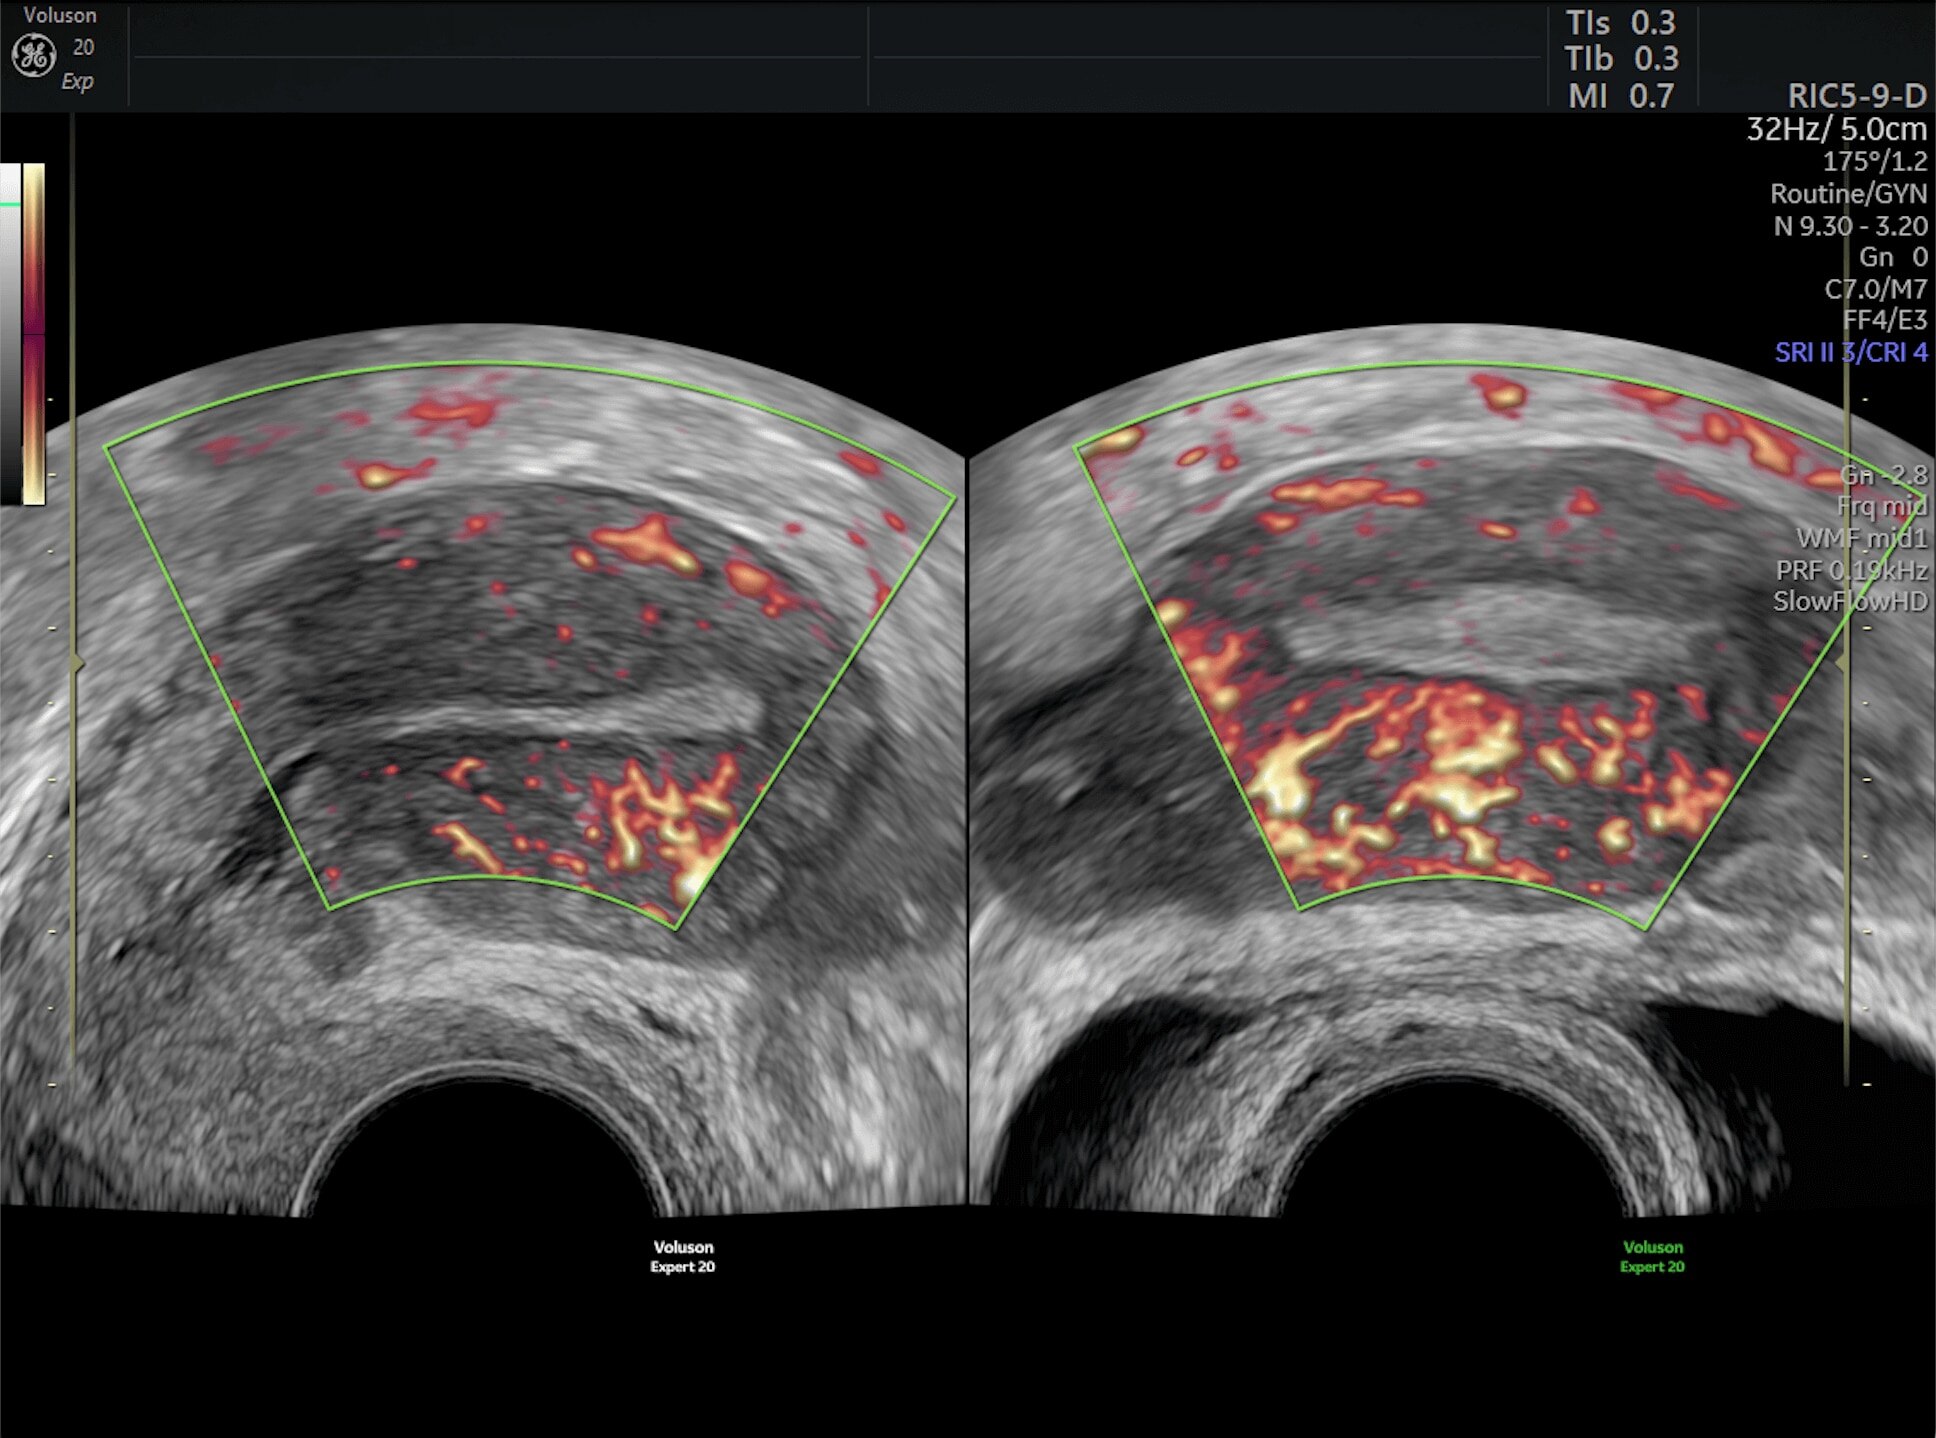

Generate spectacular 2D/3D and color Doppler images with increased penetration and stunning clarity, to help visualize critical details needed for diagnostic assurance. The Lyric Architecture unlocks new imaging and processing power to expand your imaging capabilities for years to come